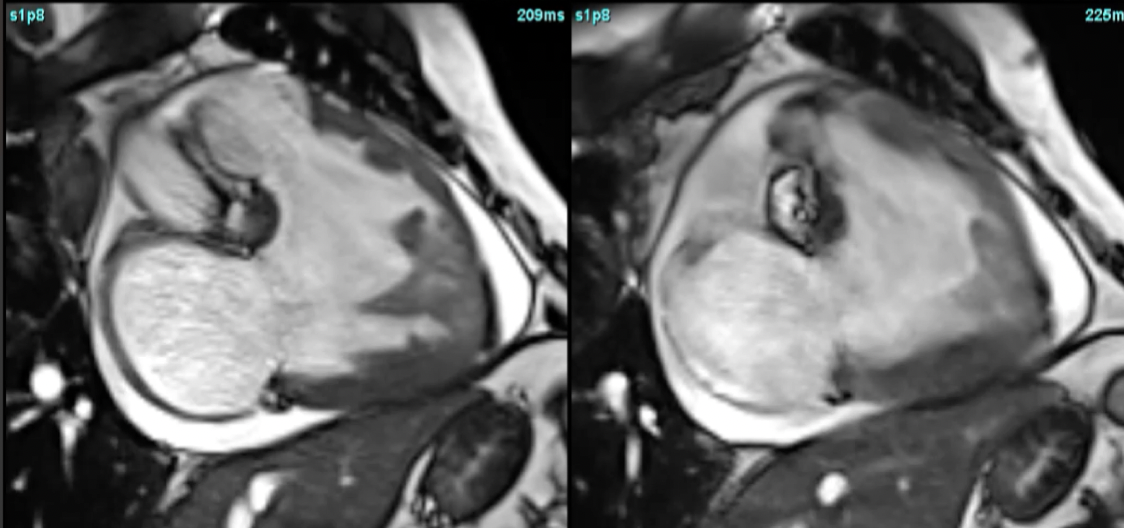

CMR for RV and PH